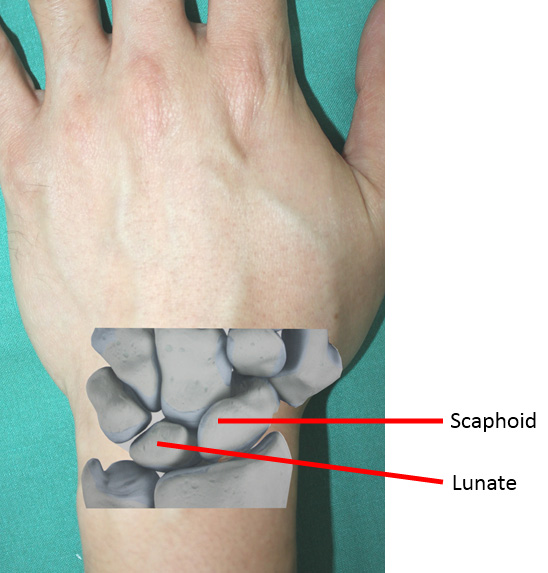

SLAC Wrist|Causes|Symptoms|Staging|Treatment|Surgery|Prevention

Radial-Sided Wrist Pain: The Scapholunate Ligament Injury – Mount …

Scapholunate Ligament Tear – Notice increase distance between scaphoid …

SNAC (Scaphoid Nonunion Advanced Collapse) – Hand – Orthobullets